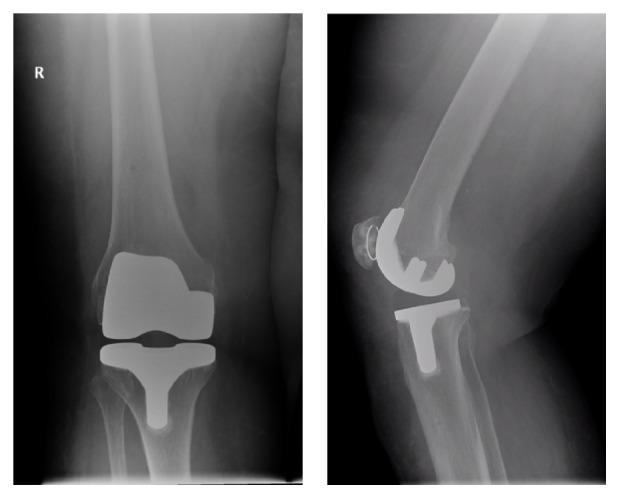

We present our case report using a novel metal artefact reduction magnetic resonance imaging (MRI) sequence to observe resolution of subchondral bone marrow lesions (BMLs), which are strongly associated with pain, in a patient after total knee replacement surgery. Large BMLs were seen preoperatively on the 3-Tesla MRI scans in a patient with severe end stage OA awaiting total knee replacement surgery. Twelve months after surgery, using a novel metal artefact reduction MRI sequence, we were able to visualize the bone-prosthesis interface and found complete resection and resolution of these BMLs. This is the first reported study in the UK to use this metal artefact reduction MRI sequence at 3-Tesla showing that resection and resolution of BMLs in this patient were associated with an improvement of pain and function after total knee replacement surgery. In this case it was associated with a clinically significant improvement of pain and function after surgery. Failure to eradicate these lesions may be a cause of persistent postoperative pain that is seen in up to 20% of patients following TKR surgery.

我们展示了一份病例报告,该报告使用了一种新型的金属伪影减少磁共振成像(MRI)序列,以观察全膝关节置换术后患者软骨下骨髓损伤(BMLs)的消退情况,这种损伤与疼痛密切相关。在一名等待全膝关节置换手术的重度终末期骨关节炎患者的3特斯拉MRI扫描中,术前可见大的BMLs。术后12个月,使用新型金属伪影减少MRI序列,我们能够观察到骨-假体界面,并发现这些BMLs已完全切除且消退。这是英国首次报道的在3特斯拉使用这种金属伪影减少MRI序列的研究,表明该患者BMLs的切除和消退与全膝关节置换术后疼痛和功能的改善相关。在本病例中,这与术后疼痛和功能的显著临床改善相关。未能根除这些损伤可能是导致TKR手术后高达20%的患者持续术后疼痛的原因。